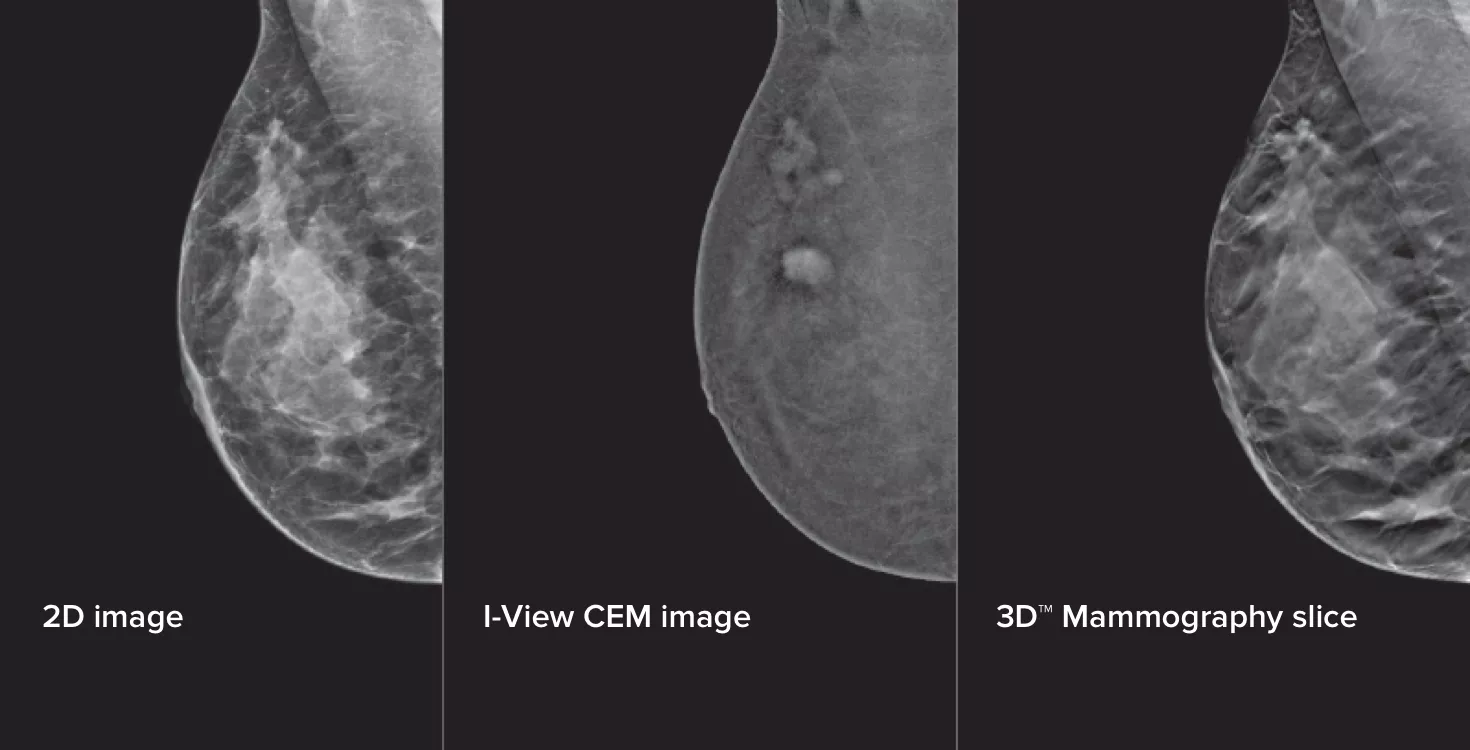

La mammografia con mezzo di contrasto (CEM), la tecnica di imaging che utilizza un contrasto iodato per rivelare le aree con maggiore afflusso di sangue, può aiutare ad evidenziare le lesioni sospette. Il software I-View permette di combinare la potenza della CEM con immagini 2D e di tomosintesi in un'unica compressione, per fornire imaging anatomico e funzionale in un solo esame.1

Questo software acquisisce informazioni anatomiche e funzionali in un unico esame, sfruttando la capacità di fornire immagini 2D, con contrasto e di tomosintesi in una sola compressione.1